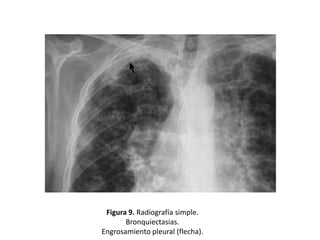

• La afectación pleural es rara, pero infecciones

engrosamiento. (Figura 9)

Figura 9. Radiografía simple.

Bronquiectasias.

Engrosamiento pleural (flecha).